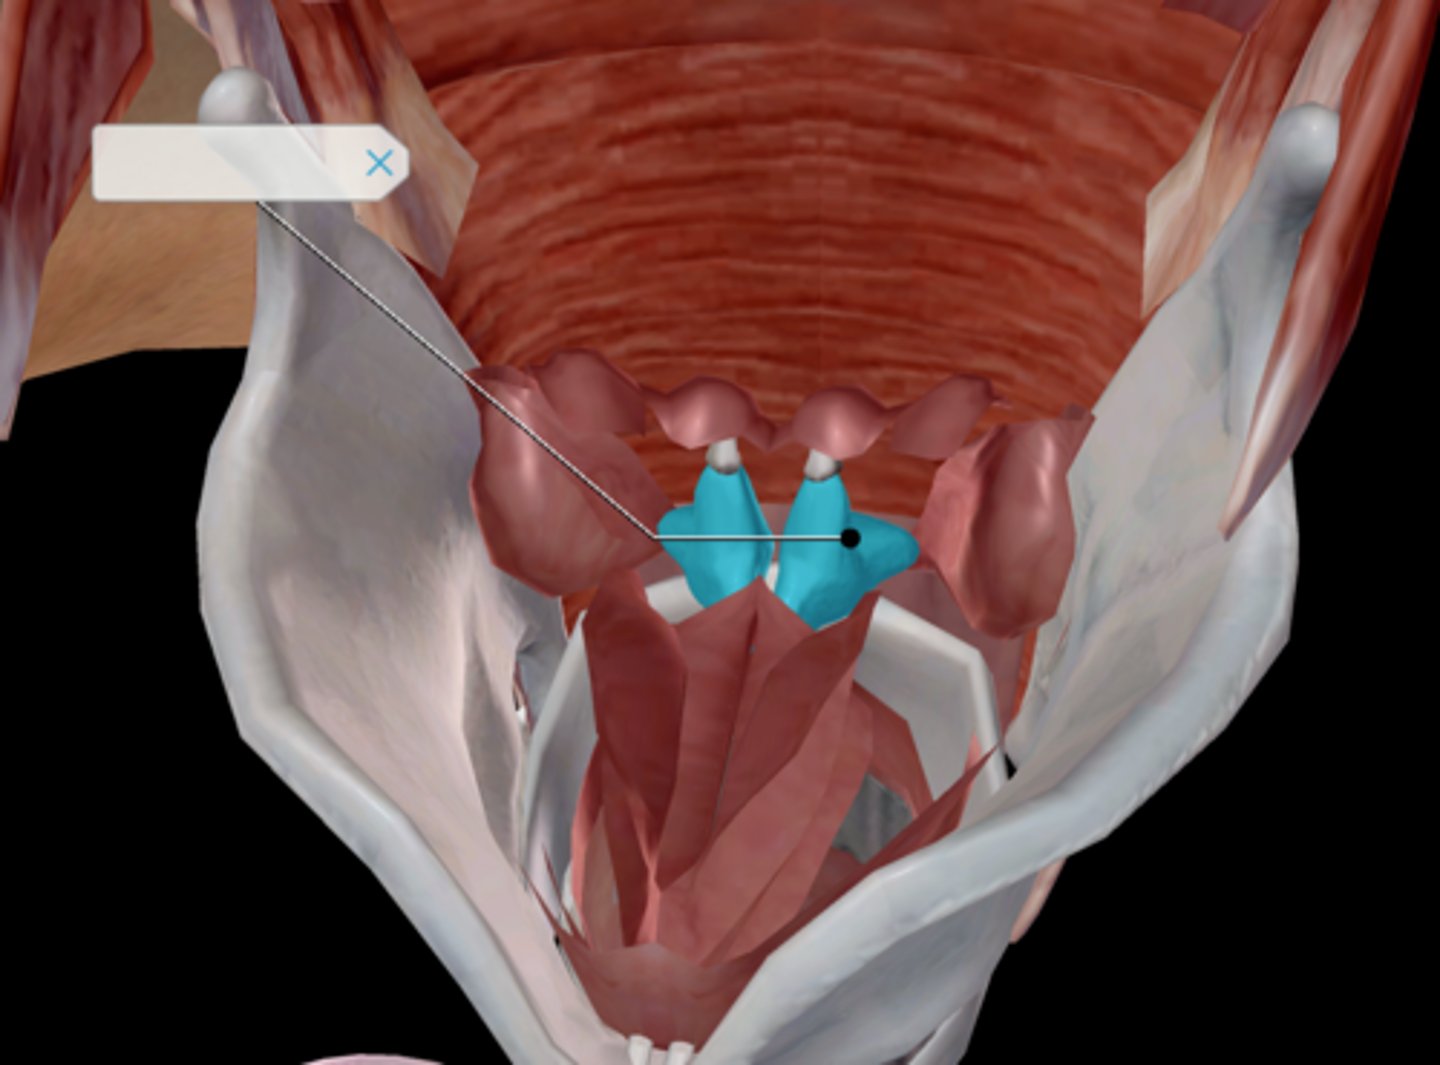

Larynx

Epiglottis

Arytenoid cartilage

Corniculate cartilage

Vocal ligament

Vocal folds

Vestibular folds